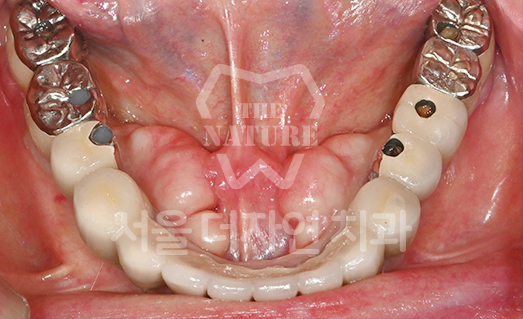

Implant Revision Surgery

Revision implant surgery is more challenging

and complex than the original procedure

Improper implant surgery or inadequate implant maintenance can lead to complications accompanied by pain. Implant revision surgery involves removing the existing implant, rebuilding the alveolar bone, reshaping the gingival contour,

and placing a new implant in the correct position.

• BEFORE: 2021.11.02

• AFTER: 2022.01.19

An implant placed at another clinic was found to be significantly mispositioned,

requiring revision surgery to correct the placement to the proper position.